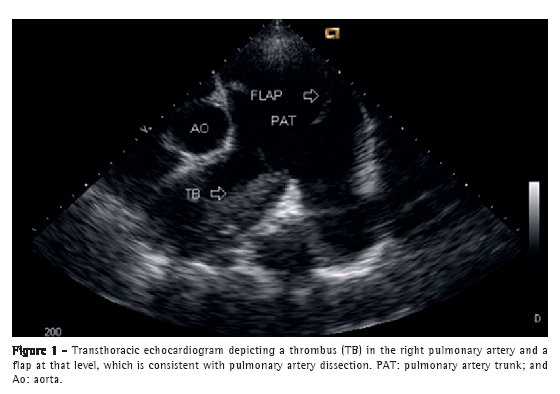

A 50-year-old male patient diagnosed four years prior with pulmonary hypertension related to schistosomiasis mansoni was admitted to the emergency room of the Federal University of Minas Gerais School of Medicine Hospital das Clínicas, located in the city of Belo Horizonte, Brazil. He presented with new onset, progressively worsening retrosternal chest pain and shortness of breath (functional class III pulmonary hypertension according to the World Health Organization). He had been diagnosed with chronic myeloid leukemia seven months prior and had since been on chemotherapy. At admission, transthoracic echocardiography revealed a large non-obstructive central thrombus in the right main pulmonary artery. The right atrium was dilated, and there was mild tricuspid regurgitation, with an estimated pulmonary artery systolic pressure of 63 mmHg. He was diagnosed as having in situ thrombosis as a complication of the long-standing pulmonary hypertension. After the possibility of acute coronary syndrome had been excluded, he was discharged on warfarin. He was re-admitted two months later due to progressively worsening, refractory chest pain. At that time, he had an SpO2 of 96%, and a third heart sound was audible at the lower left parasternal space, accompanied by a murmur of tricuspid regurgitation. The lungs were clear, and the peripheral arterial pulses were symmetric. Laboratory test results were unremarkable, including serum levels of creatine kinase, creatine kinase MB isoenzyme, and troponin. A resting electrocardiogram showed evidence of acute myocardial ischemia in the anterior leads. Transthoracic Doppler echocardiogram revealed a pulmonary artery systolic pressure of 62 mmHg, a thrombus in the right pulmonary artery, as in the previous examination, and the presence of a flap at that level that was compatible with pulmonary artery dissection (Figure 1). The diagnosis was confirmed by subsequent CT pulmonary angiography (CTPA; Figure 2). He was transferred to another cardiovascular treatment facility, where attempts were made to correct the defect with an endovascular procedure (via the femoral vein). During the perioperative period, the patient presented with refractory cardiogenic shock. Multiple efforts to resuscitate the patient were unsuccessful, and he died in the operating room.